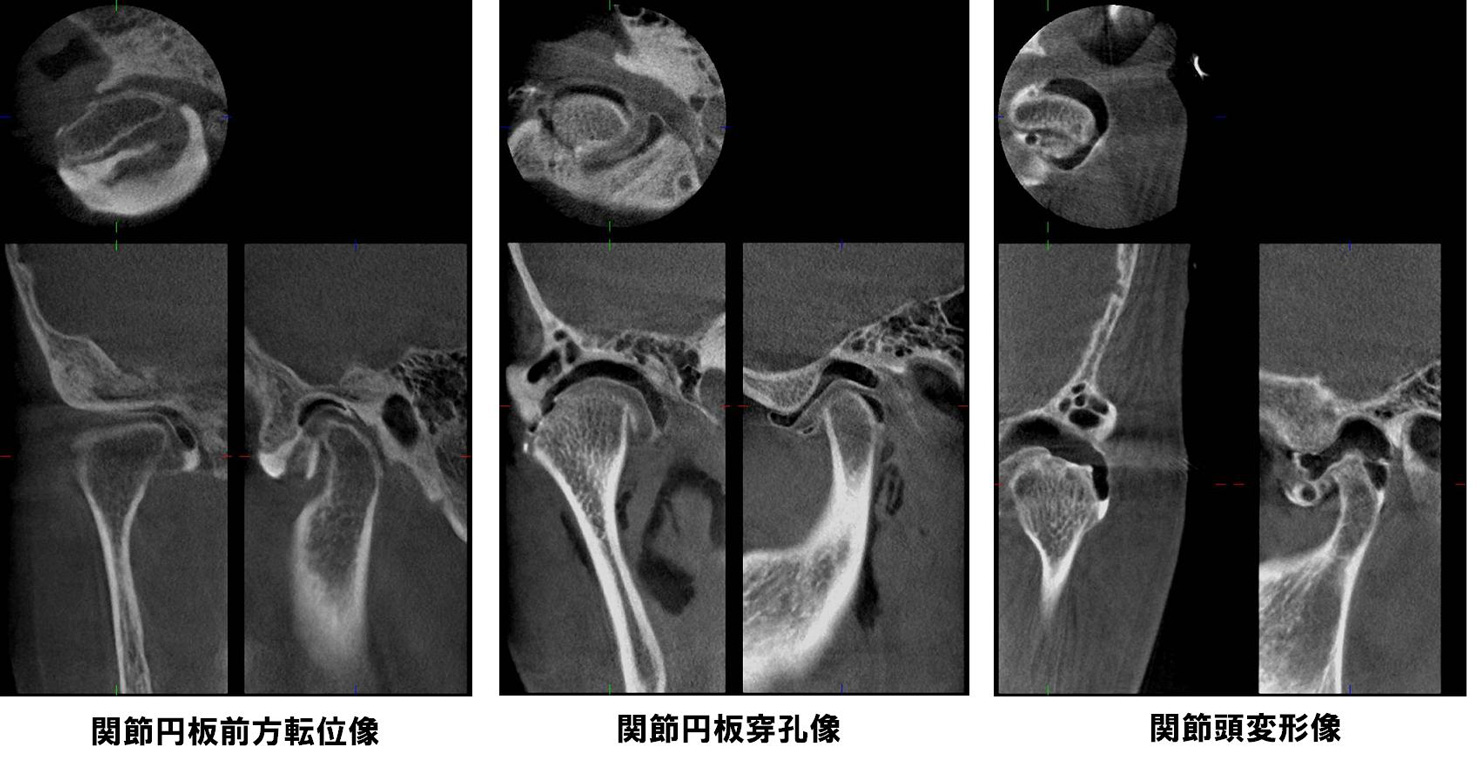

| 機能障害 | 顎関節症(注2)(注3)、顎関節強直症、顎変形症など(注2)[顎関節症] 顎関節症とは口を開けると顎の関節にカクカク音がする、顎の関節が痛い、口が開かない、顎がだるい、肩こりや頭痛がする、といった症状があり、関節雑音、開口障害、咀嚼障害を呈する疾患です。 顎関節症は正しく診断・治療すればそのほとんどが軽快しますが放置しておくと経時的に変形性関節症にまで悪化することが知られています。 当科では顎関節造影検査、関節腔内洗浄療法、スプリント療法(いずれも予約制)などの顎関節症専門外来を行っております。 |

(注2)[顎関節症]

顎関節症とは口を開けると顎の関節にカクカク音がする、顎の関節が痛い、口が開かない、顎がだるい、肩こりや頭痛がする、といった症状があり、関節雑音、開口障害、咀嚼障害を呈する疾患です。

顎関節症は正しく診断・治療すればそのほとんどが軽快しますが放置しておくと経時的に変形性関節症にまで悪化することが知られています。

当科では顎関節造影検査、関節腔内洗浄療法、スプリント療法(いずれも予約制)などの顎関節症専門外来を行っております。

当科では2008年3月よりベラビューエポックスを導入しました。この装置はパノラマ画像と3次元的歯科用CT画像が低照射量、短時間で撮影できます。歯の根尖病巣や顎骨病変、顎関節造影検査での診断やインプラント、抜歯などの術前精査において有効に用いられています。